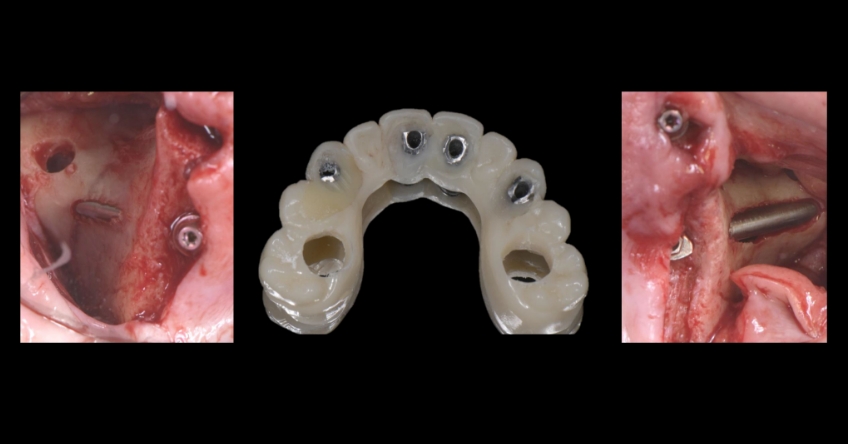

Once the patient understood the nuances between graft vs. a graft-less solution, she opted for a combination of anterior and ZIs instead of grafting the sinuses.

Ultimately, the patient was treated using a combination of traditional and zygomatic implants, allowing her to transition into the definitive prosthesis uneventfully and in a reasonable time frame. This prosthetic design aimed to improve the distribution of occlusal forces and provide enhanced structural support for the final prosthesis.